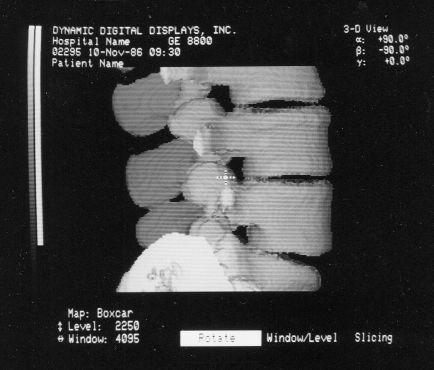

These photos of the Voxelscope II screen are typical of the types of rendering provided by the system.

Voxelscope II Screen Shots. Combination of 3-D Shaded Surface, Multiplanar Reformatting, and Segmentation

Shading for Ray Tracing (Portion of Cervical Spine)